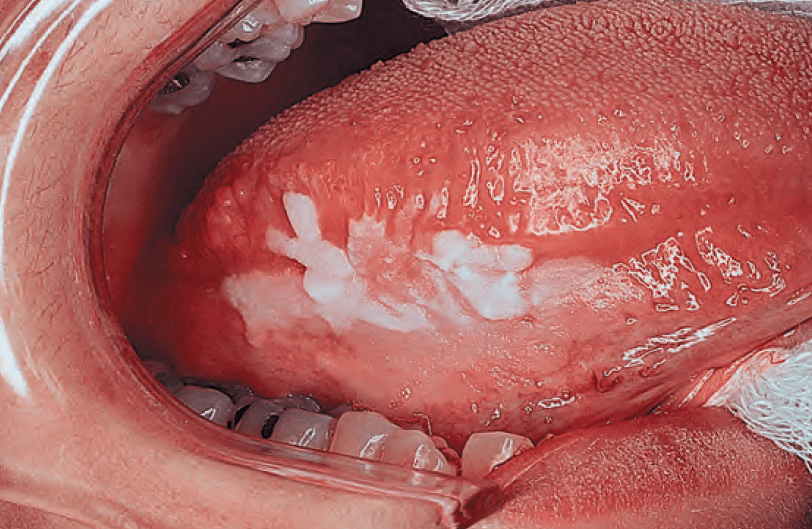

- Leukoplakia and erythroplakia:

- Are precancerous lesions that have a varying risk of progression to malignancy

- Leukoplakia develops as a result of:

- Chronic irritation of the mucous membranes by carcinogens:

- This irritation stimulates proliferation of epithelial and connective tissue

- Histopathologic examination reveals:

- Underlying hyperkeratosis associated with epithelial hyperplasia

- Keratoses of a variety of degrees:

- Manifest as leukoplakia

of the tongue